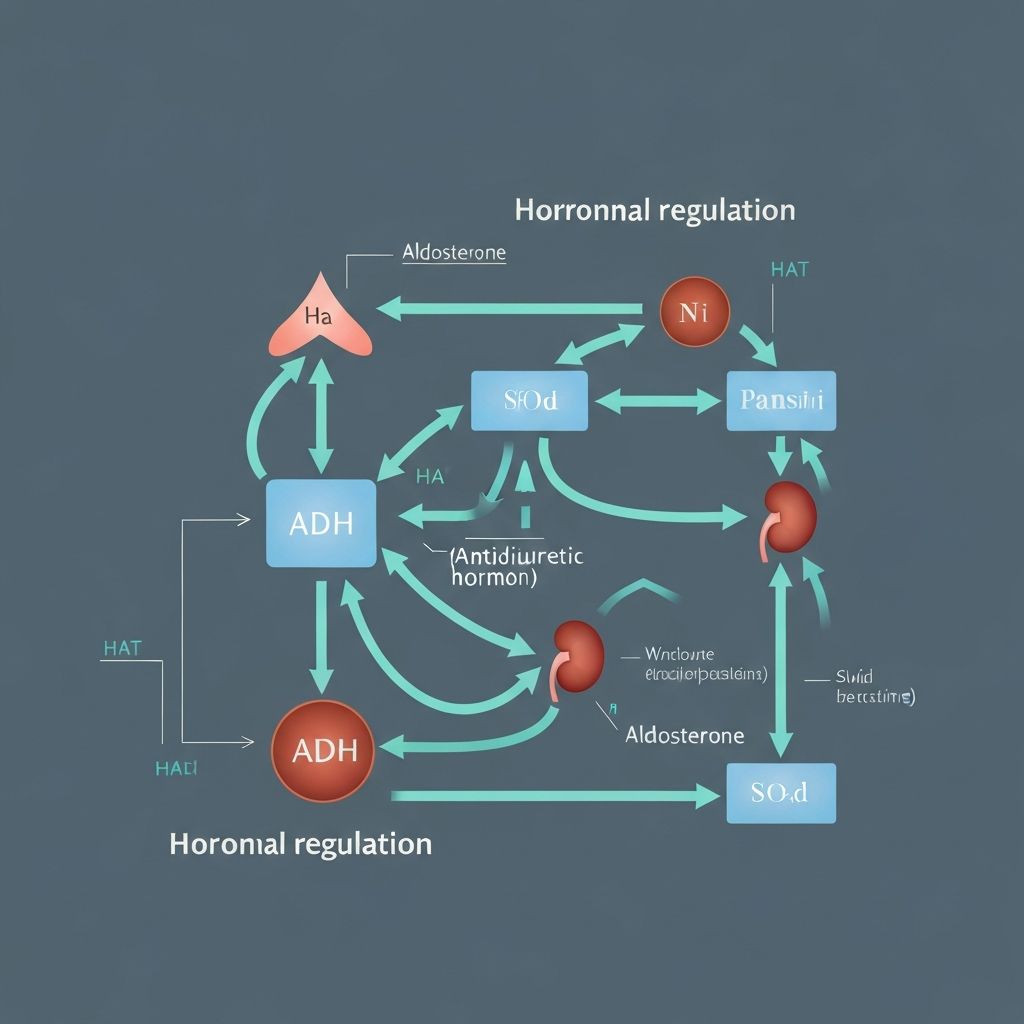

The kidneys continuously filter blood and reabsorb essential substances, including water. This process is regulated by hormones such as aldosterone and antidiuretic hormone (ADH), which respond to changes in blood osmolarity and volume. These regulatory systems ensure the body maintains appropriate fluid distribution between intracellular and extracellular compartments.